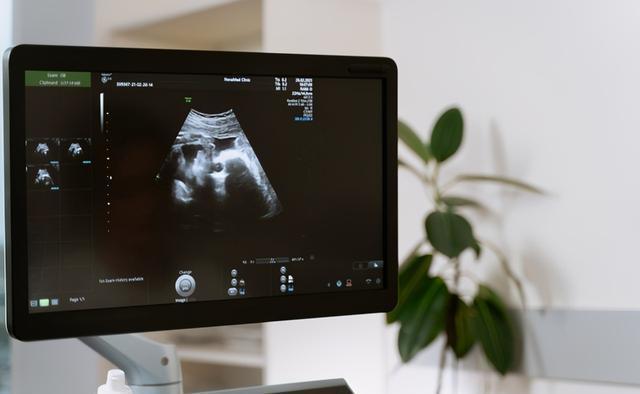

【 大排畸|大排畸能查出所有的胎儿畸形吗?一次通过大排畸的经验分享给大家】超声大排畸又叫做“孕中期产前超声筛查”,一般我们会建议在孕20-24周进行检查。

在进行超声大排畸检查时,医生会通过超声仪器检查胎宝宝在宫内的情况,包括胎宝宝各个器官和系统的发育情况、胎盘情况、羊水情况等。超声大排畸的目的在于排查胎宝宝是否存在结构性缺陷,排除先天性心脏病、唇腭裂、脊柱裂、无脑儿等重大畸形。